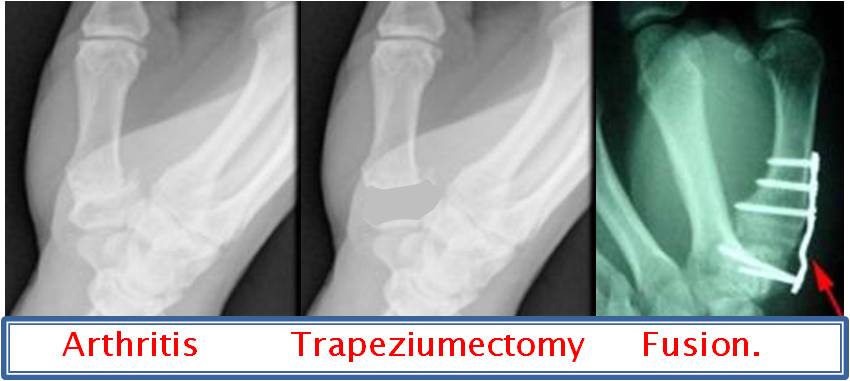

Trapeziumectomy. Most people are very well served with a trapeziumectomy. This is an operation where the trapezium bone is removed from the wrist and the gap is filled with a sling of tendon taken from the forearm.  Reports of over 95% long term satisfaction has made this the gold standard treatment for base of thumb arthritis.   Because this operation leaves you with some weakness in power and pinch grip there are some patients who are better served with a fusion.

Fusion. If you are young or a manual worker a fusion of the trapezium to the thumb

bone is sometimes preferred.  This gets rid of the pain, gives a strong pinch grip and still allows some reduced movement, in other words power at the expense of movement.